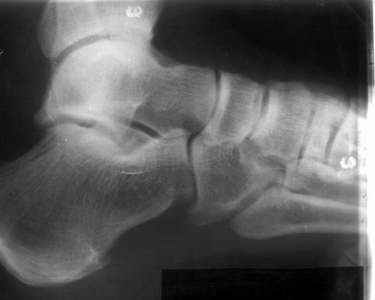

братился мужчина, 50 лет. Жалобы на боли в голеностопном суставе, периодическое подворачивание стопы вовнутрь. Получил травму 5 лет назад. При осмотре - признаки латеральной нестабильности, боли по ходу малоберцово-таранной, задней малоберцово-пяточной связки. Сделал стандартный Rg, и Rg с нагрузкой. В течение последнего года начали беспокоить боли в коленном, тазобедренном суставе. Как полагаю, это связано с нарушением биомеханики всей ноги. Если прооперировать и устранть нестабильность, пройдут ли эти боли (этот вопрос пациент задал сразу, как только услышал слово операция)? С ув. Сергей Мелашенко, Приморск, Запорожская обл. Ukraine